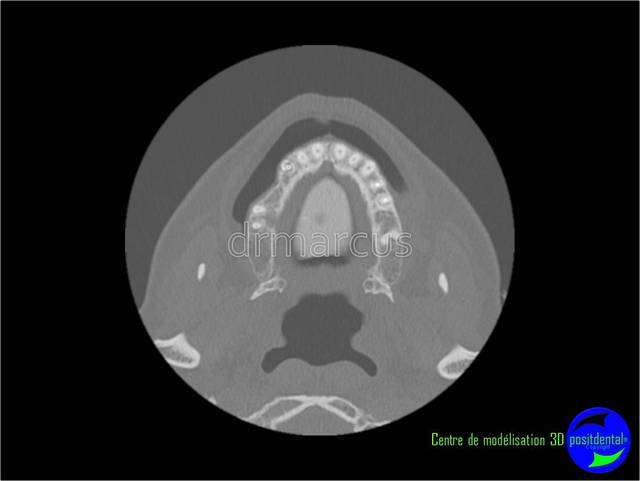

Analyse post-opératoire d’une MCI post-extractionnelle en chirurgie guidée

Cas clinique de drmarcus

Chirurgie : drmarcus

Imagerie 3D: POSITDENTAL

Guide chirurgical : POSITGUIDE

Dispositif de forage : POSITDENTAL

Implant : LEONE

Dommage que ce soit scanner avant et Cone-Beam après. Il est vrai que l’interprétation peut différer. Toutefois on voit la parfaite superposition des implants entre la planification et la réalisation. J'en conclue que le système Positdental est relativement fiable ;-))))